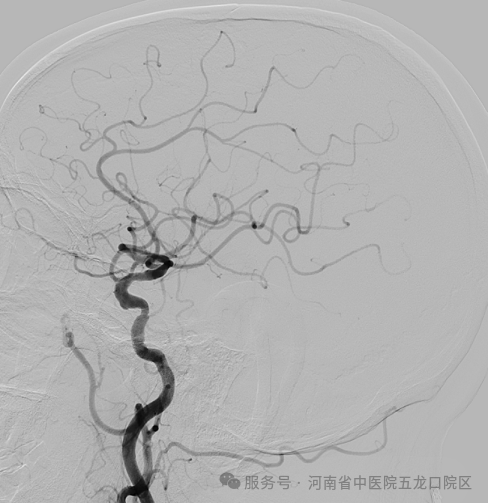

此次首例脑血管造影的顺利开展,正是科室同质化建设的重要成果。术前,程率芳主任带领团队完善术前讨论、制定周密方案;术中,姬令山副主任现场指导,团队配合默契,精准完成操作,整个过程顺利流畅,为患者后续诊疗提供了清晰可靠的诊断依据。同时,科室还响应“泛血管病”诊疗理念,联合心病科完成了脑血管-冠脉联合造影,实现了心脑血管疾病的同步评估,为合并心脑血管共病的患者提供了一站式诊疗服务。

此次首例脑血管造影的开展,只是五龙口院区脑病科规范化诊疗的一个缩影。科室依托院本部成熟的神经介入团队和卒中诊疗体系,常态化开展脑血管造影术、介入取栓术、血管内支架成形术、脑动脉瘤栓塞术等多项前沿技术,同时搭建了7×24小时卒中绿色通道,脑病科专科医师全天候值班,卒中急救电话15378761120随时畅通,为急性脑梗死、脑出血、蛛网膜下腔出血等危急重症患者争分夺秒开展积极有效的规范化救治,为守护人民群众的脑健康保驾护航!(文/郑伟锋 徐晓玉)